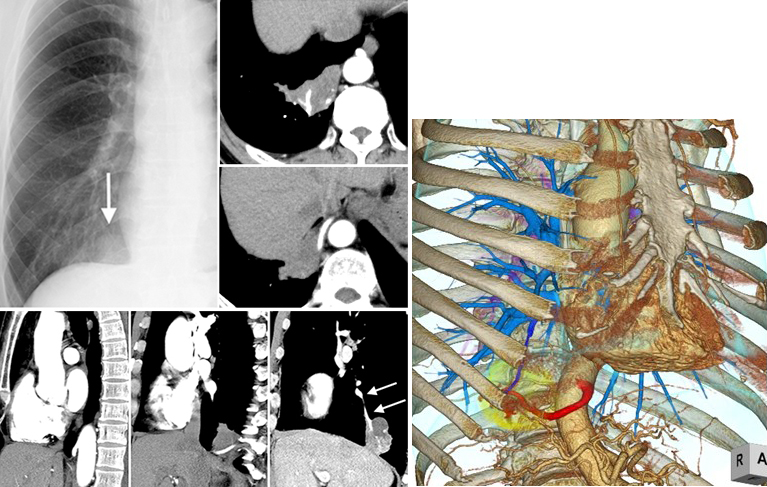

それにより若干の自覚症状と画像所 見の改善が認められるが、長期的には、生命 予後の改善はできないばかりか、かなりの症 例では副作用の発現のために予後不良となる 場合が多い(図8)。今後はピルフェニドンも 第一選択薬となり得ると思われる。 図8:特発性肺線維症の治療例 急性内科学 第10版 肺分画症の用語解説 (2)肺分画症(bronchopulmonary sequestration)概念 肺分画症は,その血流を体循環系から受け,肺実質の一部が正常肺から分離された肺の奇形であり,隣接肺との関係から肺葉内分画症と肺葉外分画症に分けられる.肺葉内分画症は分画肺が隣 肺分画症の 3dct による異常動脈の描出 21(665) が,そ れらは基本的には二次元的画像である 生体を非連続的,立体的にスキャンするヘリ カルスキャンを用いた,血管の3次元的画像化 法が開発され13),肺分画症の異常動脈の診断に

縦隔腫瘍、CCAM、肺分画症 著者 Author(s) 藤岡, 一路 / 芳本, 誠司 掲載誌・巻号・ページ Citation 周産期の画像診断 第二版,周産期医学 / 周産期医学編集 委員会編, Vol 43, 13 増刊号4486 刊行日 Issue date 1312 資源タイプ Resource Type Journal Article / 学術雑誌論文 版区分 Resource Version publisher 権利 Rights DOI肺分画症 硬化性血管腫 肺動静脈瘻・奇形 特発性肺線維症(ipf) 60歳過ぎた男性 60%以上 ほとんどの治療法は無効 死亡率は5年で50~70% 呼吸細気管支炎関連間質性肺疾患(rbild) 40~50歳 (やや男性に多い) 90%以上 禁煙、ステロイド 死亡はまれ 上に戻る 胸部レントゲン写真の所見別VR 画像を作成することで、さらに血管走行の詳細がはっきりする。 >診断 : 肺分画症( intralobar pulmonary sequestration ) >解説 : 分画肺は大動脈から分岐する異常動脈から血流を受け、以下の 2 型に分類される。原則として正常気管支とは交通がない。

行うことなく肺静脈瘤の診断と肺分画症の異常 血管の同定に有用な画像を得ることができる。 キーワード:3列adct、ダイナミック4dct、肺静 脈瘤、肺分画症 背景 ct検査の撮像時間はヘリカルスキャンの開発と検 出器の多列化により、飛躍的に短縮された療・介護関連肺炎(NHCAP ) 39/アスペルギルス感染症の病型 45/慢性進行性肺アスペルギルス症の危険因子 47/reversed halo sign51/免疫が低下した宿主の結核 61/肺結核症の分類 61/肺結核症のリスクファク ター 63/中枢気道狭窄を来す疾患 67肺底区動脈大動脈起始症 (Pryce I型肺分画症) の1例特に併走する気管支の変化と, 肺切除の必要性の有無について 平田世雄 日胸 58, , 1999 被引用文献2件

真の全肺灌流画像を得ることは64列 前マッピング,新生児肺分画症,肺毛細 血管腫症(pulmonary capillary hemangiomatosis)の画像を供覧しながら,診 断における有用性について概説する。 造影64列MDCTが 有用な胸部疾患 造影64列MDCTが有用な胸部疾患 として,肺動脈血栓,肺動静脈奇形,

症例0 肺葉内肺分画症 Ct 症例 肺 X線写真

症例084 肺葉外肺分画症 Ct 症例 X線写真 アトラス